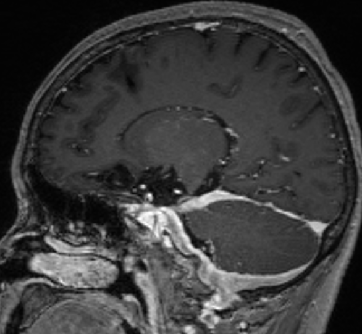

2013-5-16 MRI